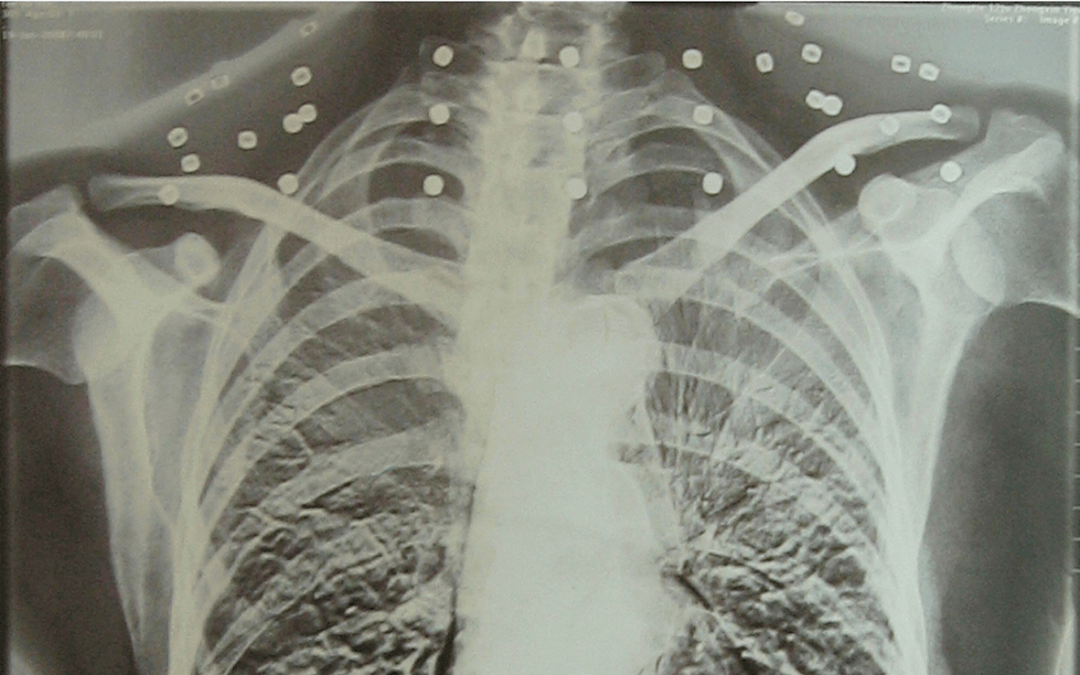

这张照片

是今年82岁的吴以先老人

拍摄的一张CT照

吴以先的颈部和腹部

共分布着33枚弹片

皇冠登一登二登三区别他体内的弹片都没有取出

身体留有弹片的位置就有痛感

在皇冠登一登二登三区别他看来

这是皇冠登一登二登三区别他与战友并肩作战的见证

是皇冠登一登二登三区别他的勋章